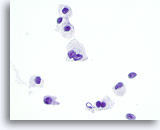

Deze catergorie omvat in ons lab ook monsters waarvan de voorspellende waarde van maligniteit bij histologie minder dan 50% is (meestal minder dan 30%) en hoger dan 10%.[6, 7] Dit omvat die monsters die een paar kenmerken vertonen van papillair carcinoom, maar die onvoldoende zijn voor een diagnose. [7] De positieve voorspellende waarde hiervan varieert in de literatuur van 20 tot 54%. [7, 9, 10, 11] Deze laesies vertegenwoordigen vaak de folliculaire variant van papillair carcinoom. In deze diagnostische categorie vallen ook folliculaire en Hürthle celneoplasma’s, die worden gekenmerkt door weinig colloïde en folliculaire cellen in microfollikels en opeengepakte groepen of losse Hürthle-cellen. De positieve voorspellende waarde van deze laesies voor een carcinoom varieerde in de literatuur van 2 tot 91%,[6, 9, 10, 12, 13, 14, 15, 16, 17, 18, 19, 20, 21, 22, 23, 24, 25, 26, 27]waarschijnlijk als gevolg van verschillende definities van deze termen en wisselende criteria die worden gebruikt voor het schema en bij de histologische diagnose. Bij de meeste rapporten is deze waarde minder dan 30%. [10, 15, 22, 24, 27]

Zeer waarschijnlijk benigne

In deze categorie vallen die folliculaire laesies die een macrofolliculair of gemengd micro- en macrofolliculair patroon vertonen met weinig tot overvloedig colloïde op de achtergrond. Op ThinPrep zijn macrofollikels te zien als lagen van tientallen gelijkmatig verdeelde folliculaire cellen met een goede afstand tussen kernen. De significantie van losse folliculaire cellen op ThinPrep in onzeker, omdat deze worden waargenomen in een verder micro- of macrofolliculair patroon. Omdat de waarschijnlijkheid dat deze laesies maligniteit vertonen (folliculaire variant van papillair carcinoom of folliculair carcinoom) bij histologie laag is, maar niet helemaal nul (in de literatuur varieert het percentage van 0 tot 43%) [6, 9, 12, 13, 14, 15, 16, 17, 18, 19, 20, 21, 24, 25, 26, 27] waarbij op drie na[14, 16, 27] alle studies minder dan 6% rapporteerden, noemen we dit daarom zeer waarschijnlijk benigne in plaats van onmiskenbaar benigne.